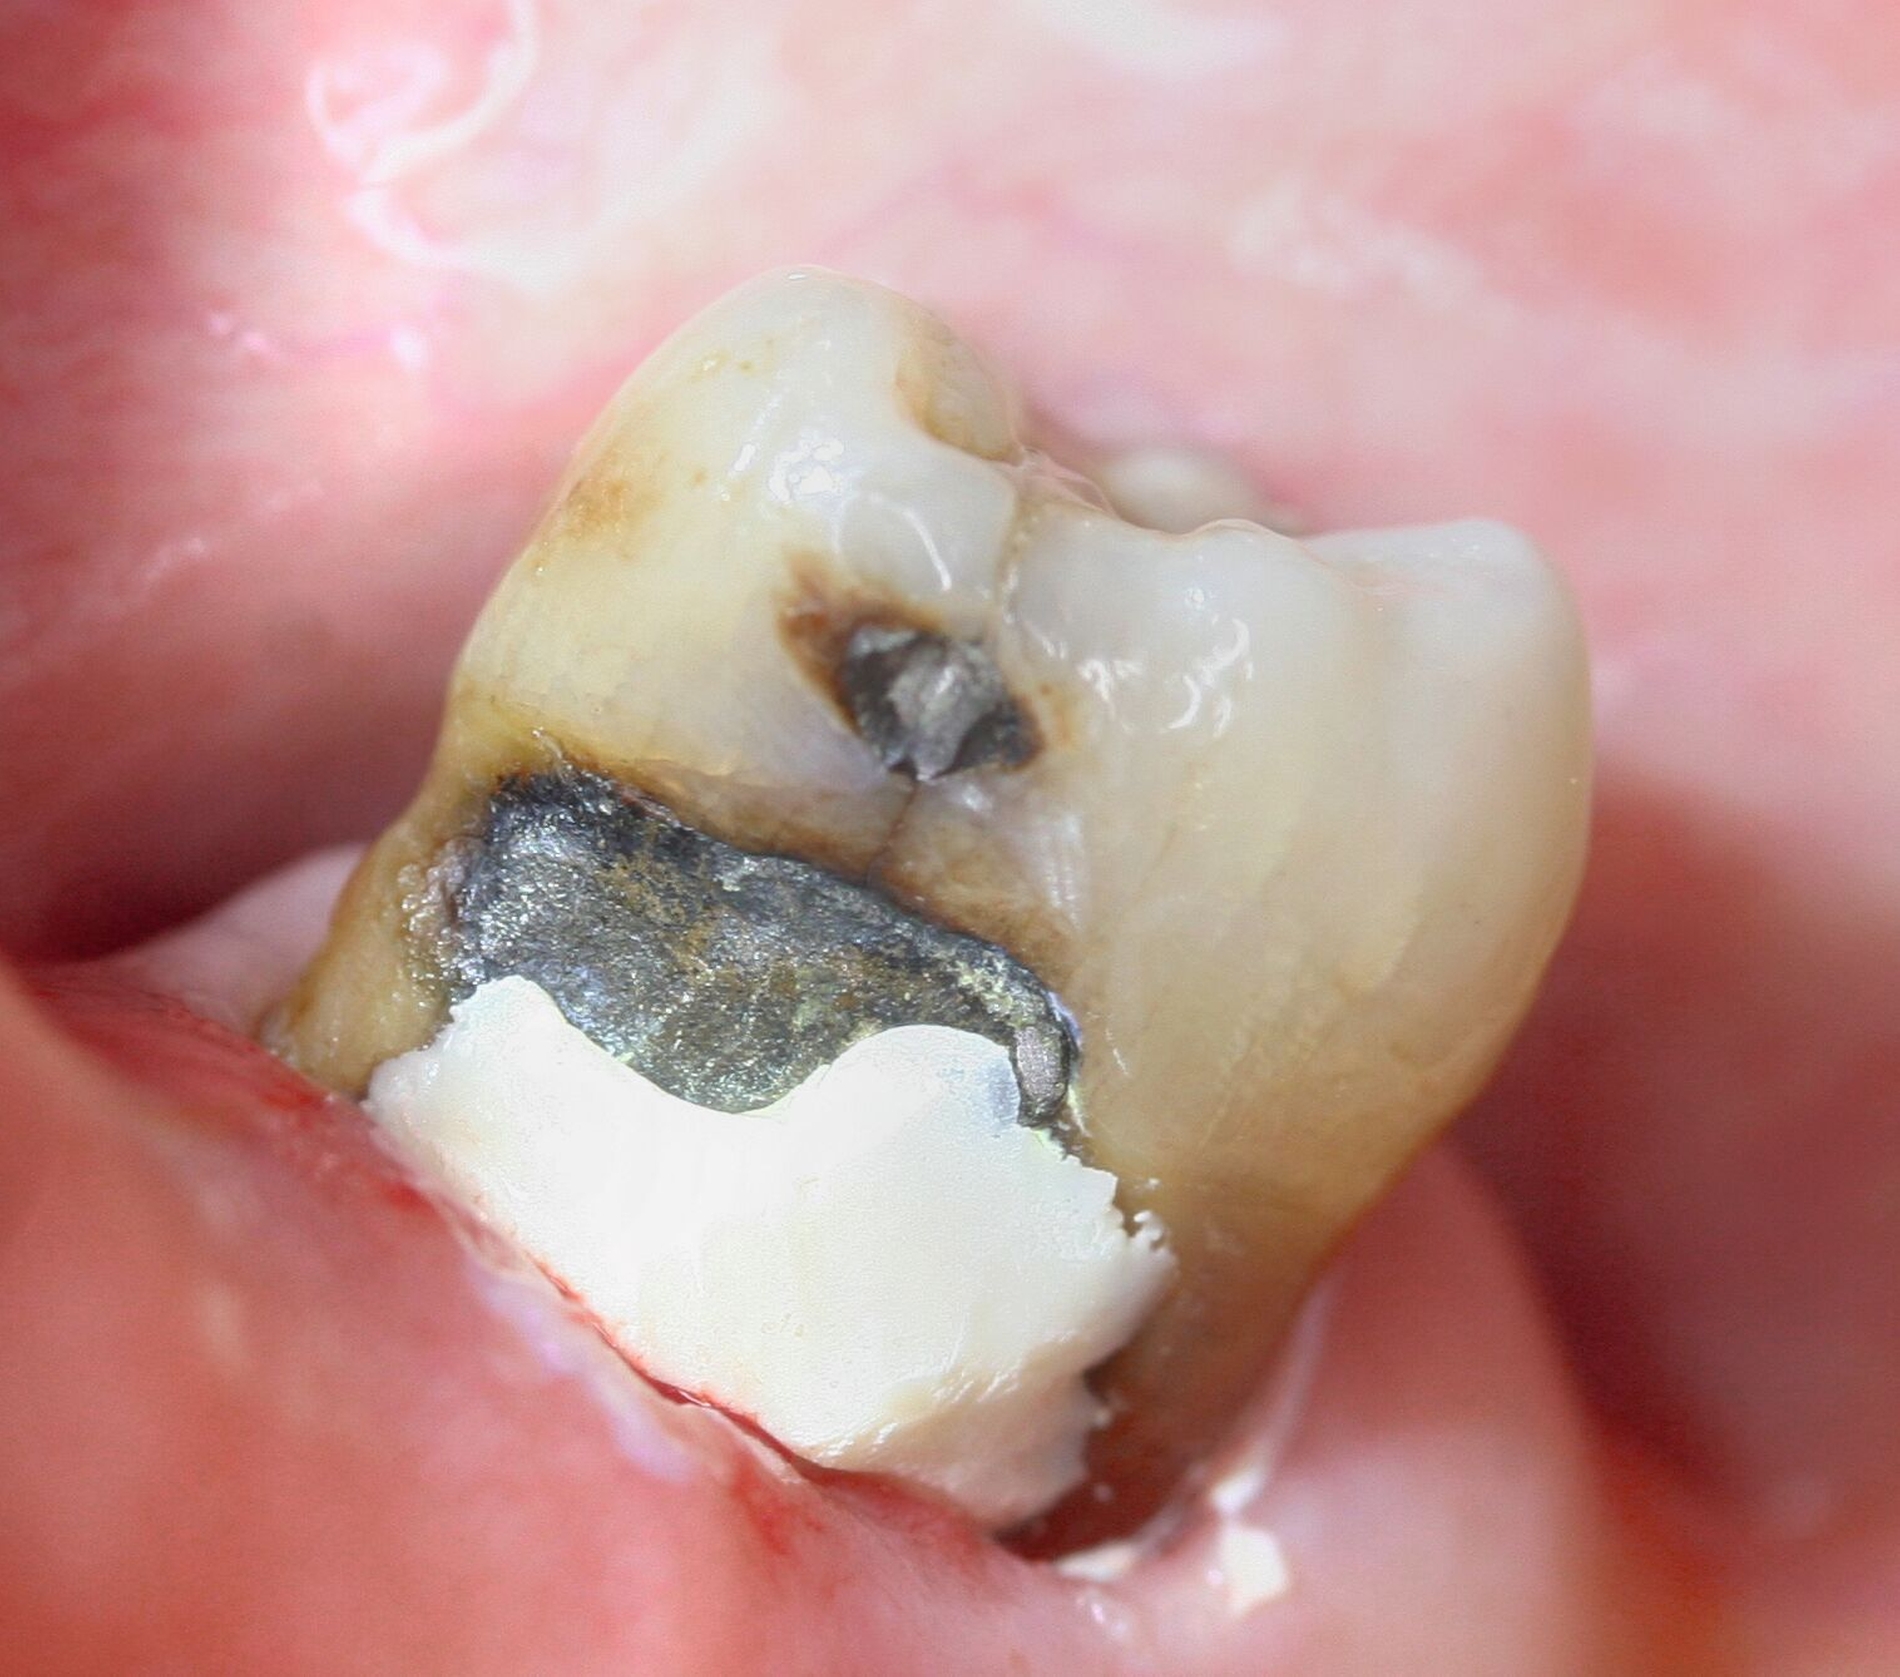

SDF ist besonders wirksam bei der Behandlung von Kariesläsionen (Abbildung 1). Bei der Anwendung auf kariösem Zahnhartgewebe dringen die Silberionen in die bakteriellen Zellwände ein, stören die bakterielle DNA-Synthese und den Stoffwechsel, und führen so zum Zelltod. Zusätzlich stabilisieren die Silberionen die kariösen Läsionen, indem sie die Dentinkanälchen blockieren (Abbildung 2) [Crystal, and Niederman, 2019].

Der verkürzt dargestellte Patientenfall zeigt dieses minimalinvasive, innovative und kostengünstige Behandlungskonzept [Ahmed et al., 2023]. Im Kern werden dazu nach vorheriger Diagnostik orthodontische Separiergummis in die Zahnzwischenräume eingesetzt und für circa ein bis zwei Stunden in situ belassen. Direkt nach der Entfernung der Gummis erfolgt eine zügige, direkte klinische Untersuchung der Approximalkaries und eine Applikation von SDF zur Kariesinaktivierung mittels Microbrush.

Der Patientenfall belegt röntgenologisch die hohe Kariesaktivität vor der Behandlung, sowie die deutlich reduzierte Kariesaktivität nach der einmaligen SDF-Applikation in der oben genannten Technik nach knapp eineinhalb Jahren anhand von Bissflügelaufnahmen (Abbildungen 8a bis 8g). Eine retrospektive Pilot-Untersuchung an der Kinderzahnheilkunde in Greifswald gibt deutliche Hinweise auf die Wirksamkeit dieser Technik. Die Ergebnisse wurden beim diesjährigen Weltkarieskongress vorgestellt und diese Studie wurde ebenfalls von ORCA prämiert. Die Ergebnisse dieses Pilotprojekts zeigen für gut 90 Prozent der behandelten E1/E2/D1-Läsionen über einem Zeitraum von 15 Monaten keine weitere Progression in den Bissflügelaufnahmen [Ahmed et al., 2024].